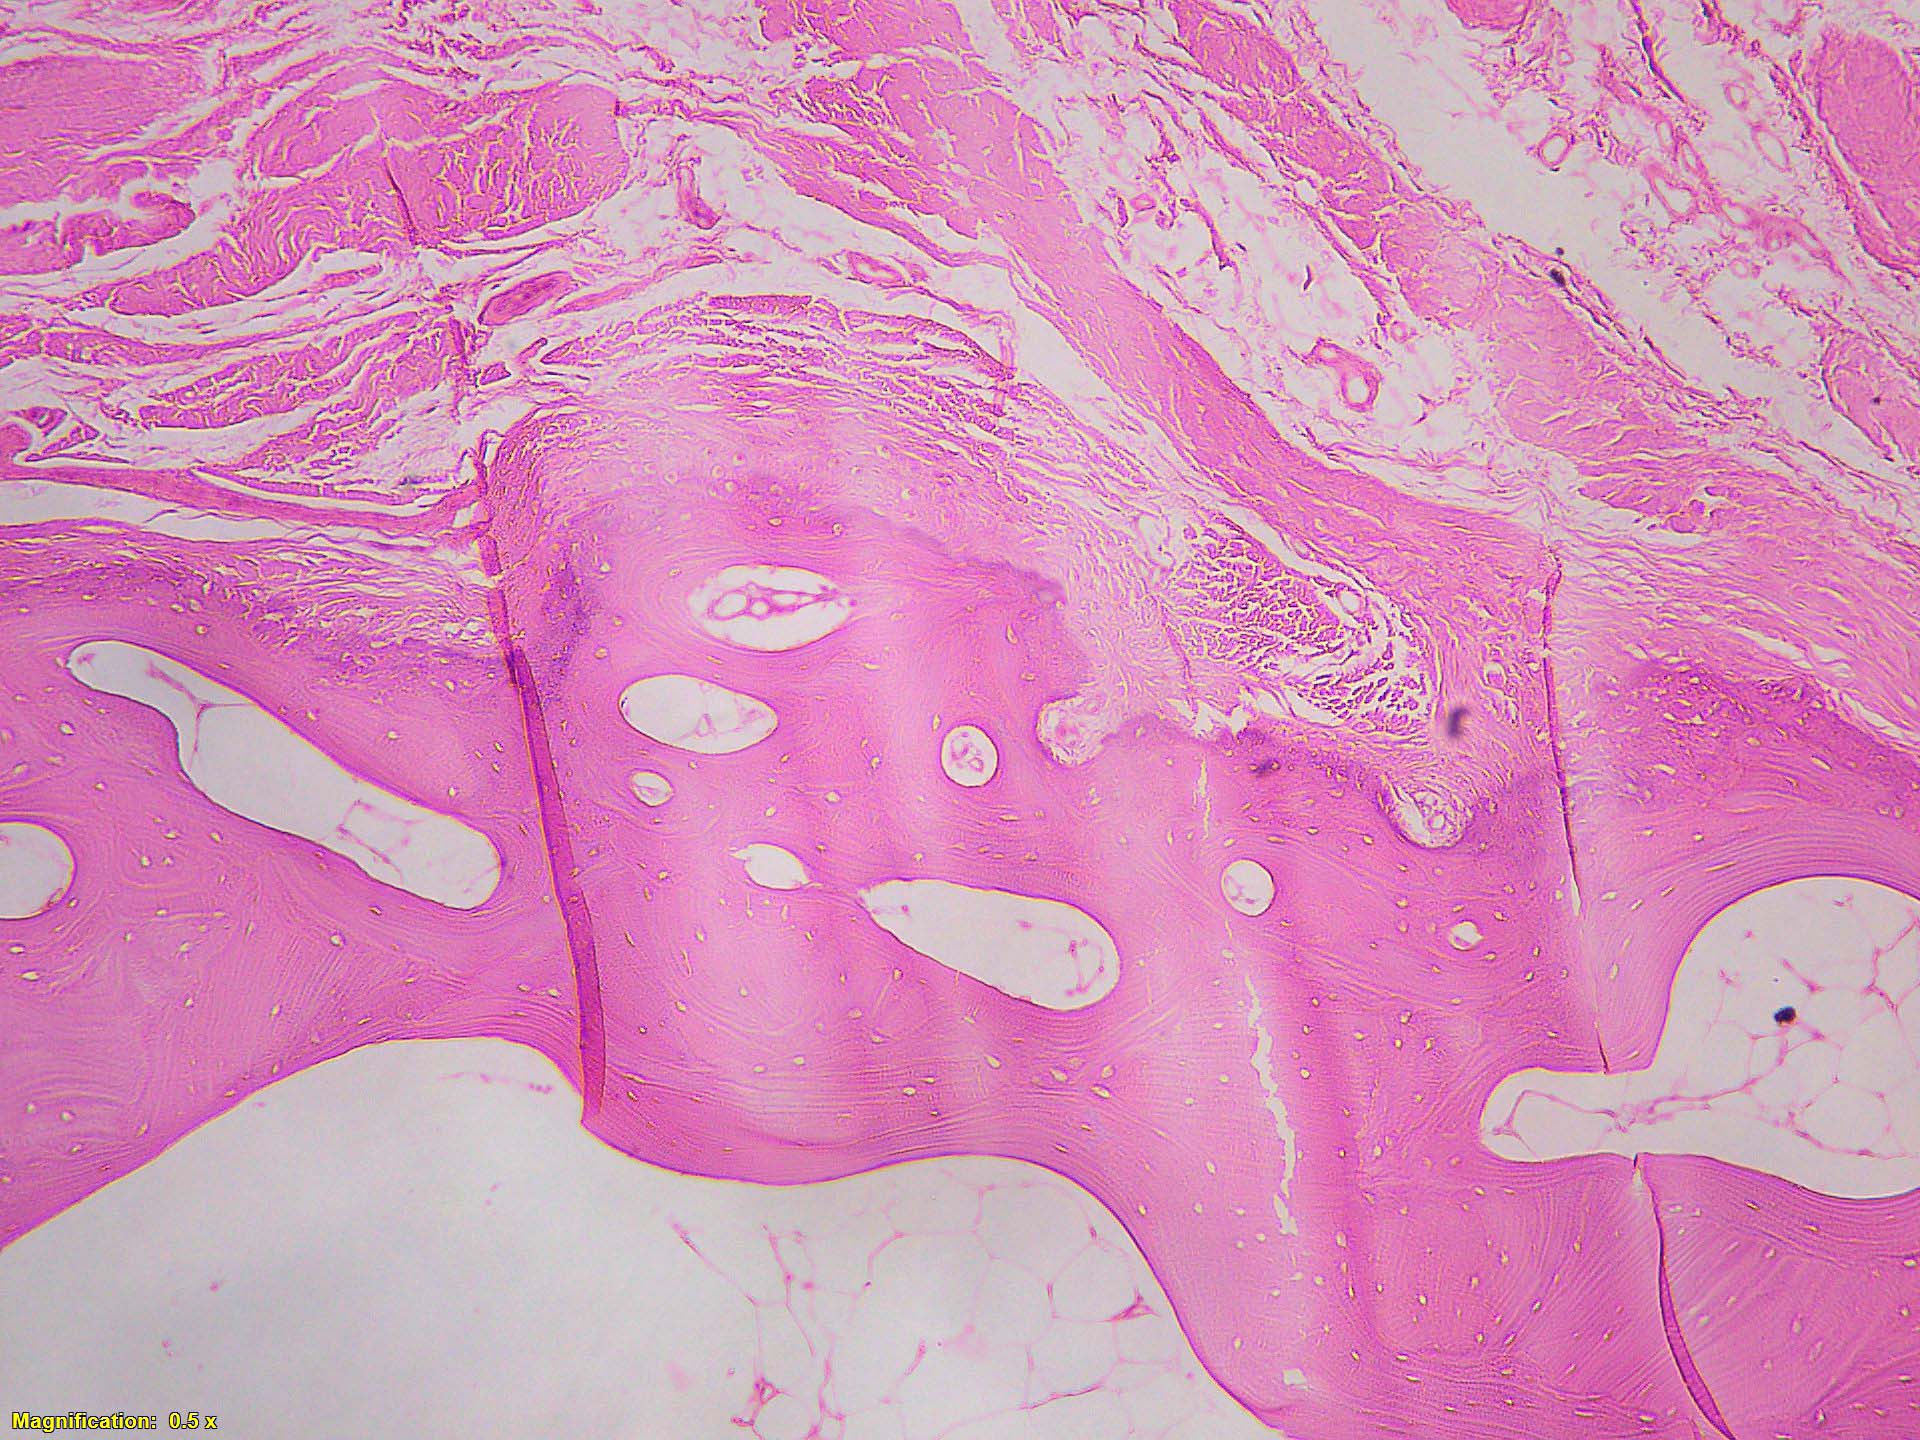

Microscopic (histologic) description

- Histologically, zonal pattern is characteristic with different degrees of cellular differentiation (inner zone, intermediate zone and peripheral zone)

- Inner central zone:

- Composed of fibroblastic / myofibroblastic proliferation, which is richly vascular, rich in inflammatory cells and resembles nodular fasciitis; some multinucleated giant cells may also be seen

- Cells show mild degree of pleomorphism and brisk mitosis

- Areas of hemorrhage, fibrin, endothelial proliferation and entrapped atrophic muscle fibers are noted

- Intermediate zone:

- There is a mixture of fibroblasts and osteoblasts along with erratic osteoid separated by small sized vessels

- Scattered chondrocytes may be appreciated

- Peripheral zone:

- Osteoid undergoes calcification and leads to lamellar bone formation

- Islands of mature or immature cartilage may be present

- Extreme periphery / margin shows mature bone with osteoblastic rimming and little to no pleomorphism

- Lesion is separated from the normal tissue (muscle) by a zone of loose, myxoid fibrous tissue

- Inner central zone:

- Early stage (0 - 4 weeks):

- Mass shows central zone morphology with only rare foci showing osteoid

- Zonal pattern is not very much appreciated

- Intermediate stage (4 - 8 weeks):

- Zonal pattern is appreciated with central zone, intermediate zone and peripheral zone

- Late, mature stage (> 8 weeks):

- Mass is mostly composed of mature bone

- Very old lesions show only lamellar bone separated by fibrovascular stroma, mimicking osteoma

- References: Curr Sports Med Rep 2018;17:290, Goldblum: Enzinger and Weiss's Soft Tissue Tumors, 7th Edition, 2019, Exp Ther Med 2021;21:531, Mol Clin Oncol 2018;8:749, Autops Case Rep 2021;11:e2021316

Microscopic (histologic) images

A 36 year old boxer presented with a painful mass in the right arm for the last 1.5 months. On radiology, an intramuscular mass was seen with peripheral mineralization and central latency. It was biopsied, which showed the morphology in the image above. What is the most likely diagnosis?

B. Myositis ossificans. The given history in this case shows that the patient is physically active and provides short duration history of the lesion. The radiological findings suggest a lesion with maturation at periphery. The microscopic image shows characteristic zonation. These are all features of myositis ossificans.